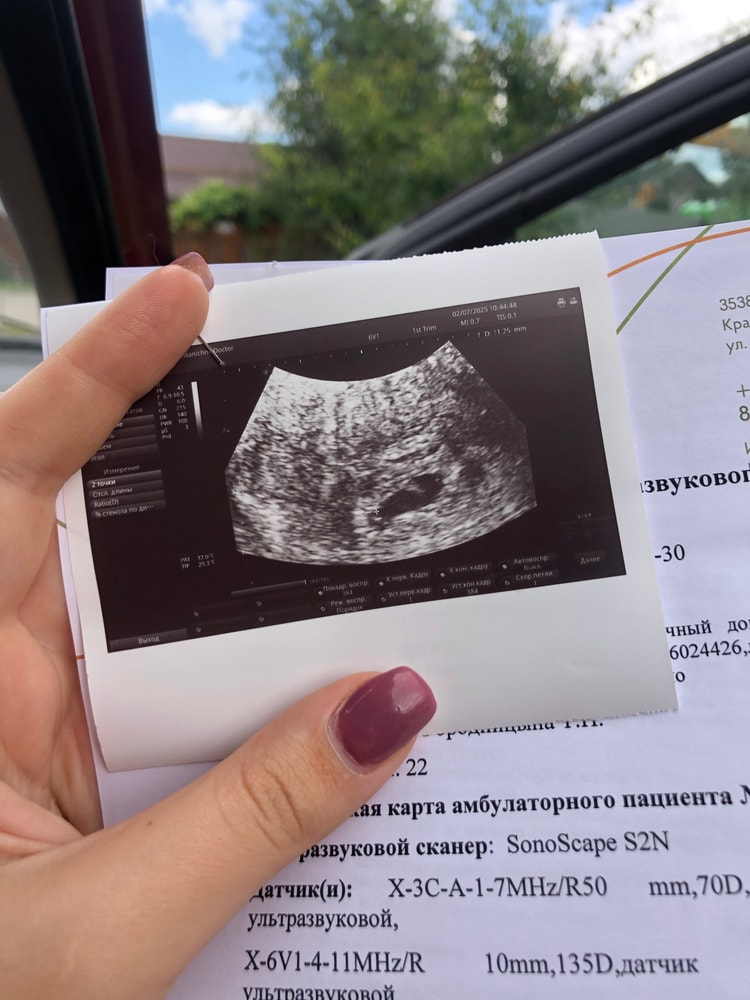

Прошу советаТолько сейчас заметила что в воскресенье 3 дня назад желточный мешочек был 2.9 сегодня на узи 2.2. Делала в разных местах. Он что может так уменьшаться? Или это узисты так смотрят. Я чет не пойму сейчас. 🤔

Беркана, здравствуйте 😁 ну 3 дня назад я делала в платной новой клинике нашего города с новыми хорошими аппаратом. Сегодня в жк 😁 ну а днем в больнице тут вообще сказали желточного мешка нет 🤷

Юлия, в больнице мне вообще какую-то фигню пронесли что желточного мешка нет 🤦 мой шок в шоке. Сказали что беременность аномальная